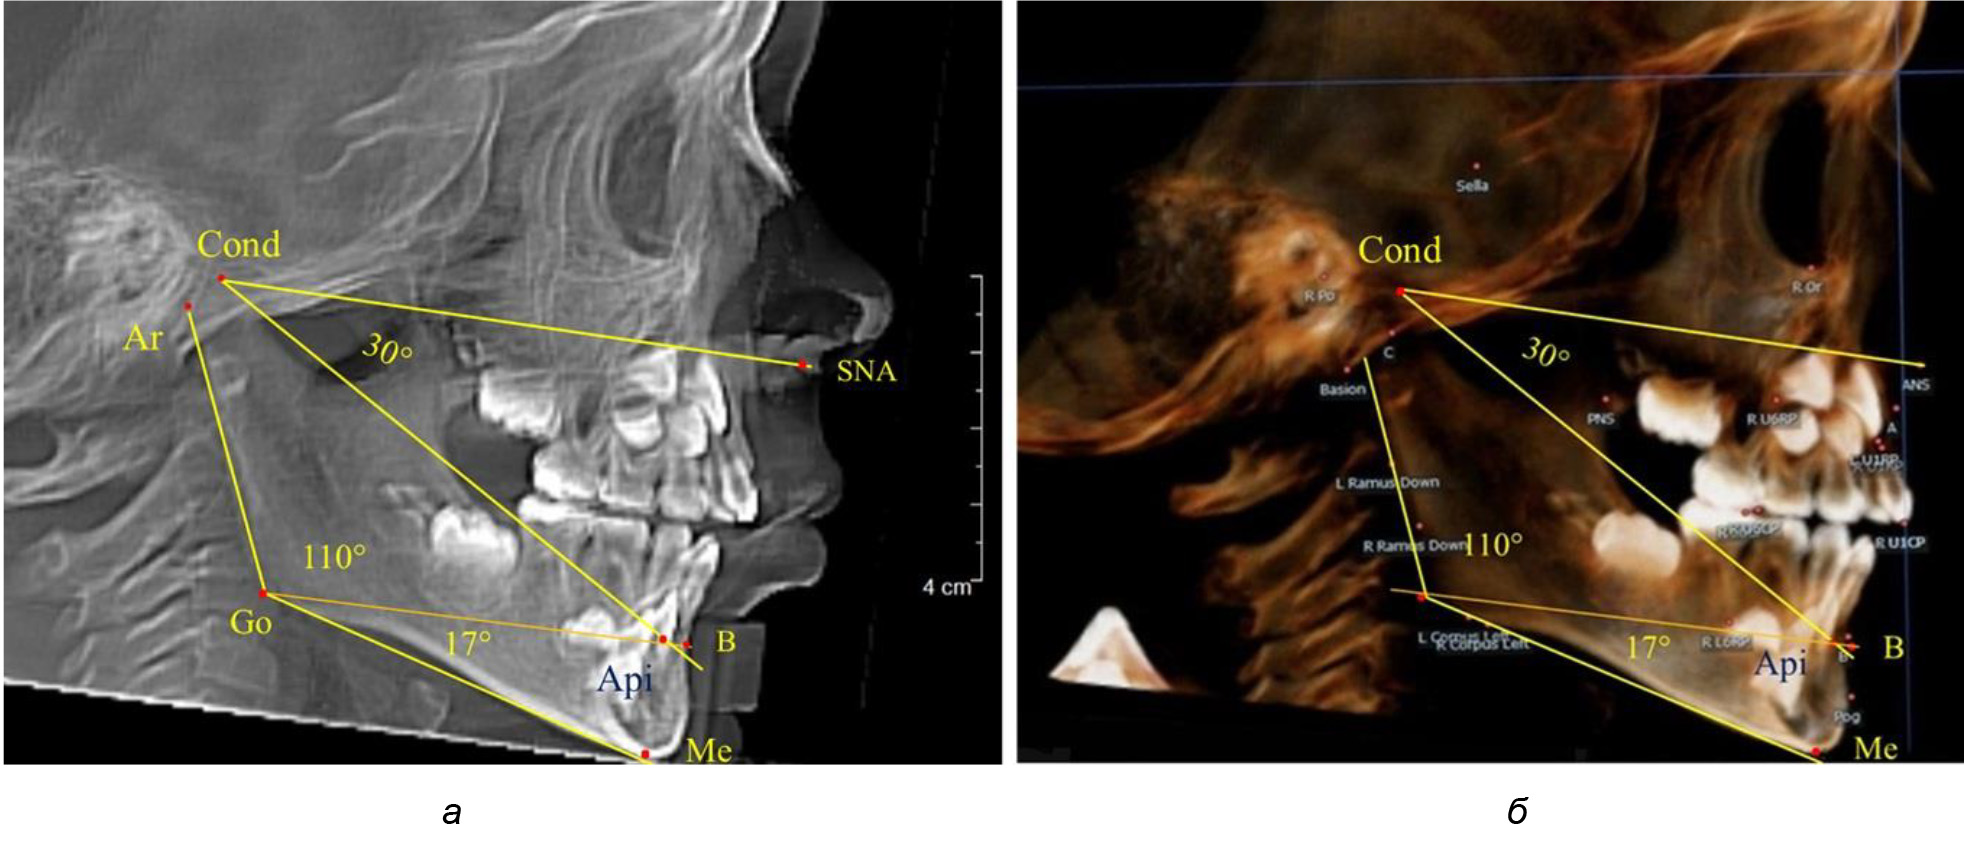

При анализе ТРГ 5 детей в периоде прикуса молочных зубов отмечено, что величина основного угла гнатической части лица SNA-Cond-Api, как правило, в норме составляла около 30°, и его величина была относительно стабильной у всех обследованных детей. В то же время угол нижней челюсти и его составляющие отличались вариабельностью параметров при различных показателях нижнечелюстного угла (рис. 4).

Рис. 4. Особенности ТРГ (а) и 3D-модели (б) в периоде прикуса молочных зубов

Таким образом, в периоде молочного прикуса с оптимальными окклюзионными соотношениями, несмотря на линейные размеры в вертикальном и сагиттальном направлении, которые, безусловно, меньше параметров взрослых людей, величина основного угла гнатической части лица SNA-Cond-Api соответствовала параметрам людей с полностью сформированным физиологическим прикусом постоянных зубов. Анализируя данные рентгенограмм детей в периоде сменного прикуса, отмечено, что величина основного угла гнатической части лица SNA-Cond-Api, так же как в молочном и постоянном прикусе, в норме составляла от 28 до 32°. В то же время угол нижней челюсти и его составляющие отличались вариабельностью параметров при различных показателях нижнечелюстного угла. Достоверных различий угла гнатической части после смены нижних медиальных резцов и прорезывания первых постоянных моляров (4 ребенка) не было; происходил очередной этап подъема высоты прикуса и увеличение линейных размеров костей гнатической части, однако угловые параметры были относительно стабильны. После смены всех резцов и замены первых молочных моляров первыми премолярами (6 человек) увеличивались линейные размеры при сохранившихся угловых показателях гнатической части лица (рис. 5).